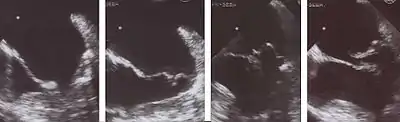

The diagnosis of MVP depends upon echocardiography, which uses ultrasound to visualize the mitral valve.

Echocardiography is the most useful method of diagnosing a prolapsed mitral valve. Two- and three-dimensional echocardiography is particularly valuable as they allow visualization of the mitral leaflets relative to the mitral annulus. This allows measurement of the leaflet thickness and their displacement relative to the annulus. Thickening of the mitral leaflets >5 mm and leaflet displacement >2 mm above the annular plane in parasternal long-axis view indicates classic mitral valve prolapse.[27]